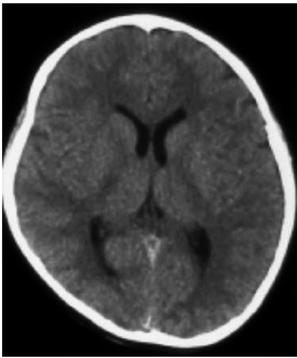

辅助检查:血常规(2010年10月21日):白细胞10.86×109/L,中性粒细胞0.83,血红蛋白129g/L,血小板301×109/L。颅脑CT平扫(2010年10月25日,图2):脑室系统饱满,双侧脑室后角室管膜下血管影显著,余颅脑平扫未见异常。超声(小器官)(2010年8月3日)检查结果:右侧髂腰肌内、髂外动静脉周围及腹股沟区皮下大片蜂窝状无回声区,考虑血管瘤。

图2 第二次颅脑CT检查(2010年10月25日):未见明显脑室及蛛网膜下腔出血